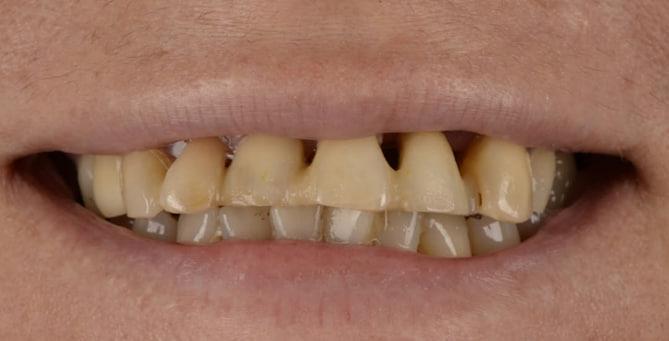

Повна двощелепна реабілітація на імплантатах

Олександр, 53 роки

Втрата зубів та кісткової тканини навколо зубів, в результаті захворювання ясен - парадонтиту. Порушення функції, естетики та якості життя.